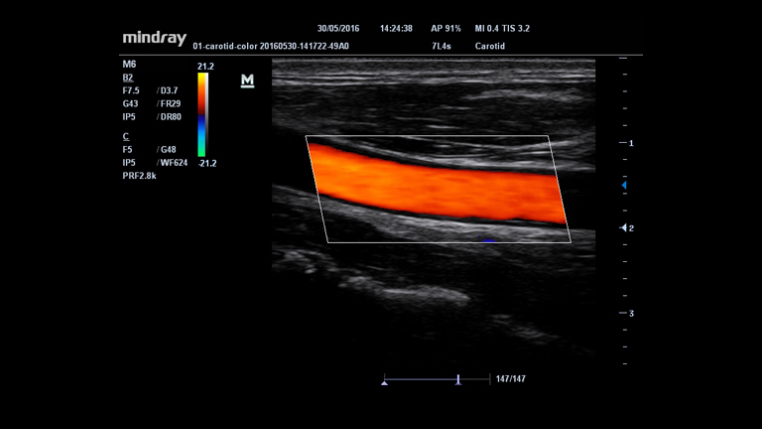

Auto IMT (automatyczny pomiar kompleksu Intima-Media)

Automatyczny pomiar grubo?ci kompleksu Intima-Media na przedniej i tylnej ?cianie naczynia, zapewniaj?cy precyzj? badania stanu t?tnicy szyjnej.